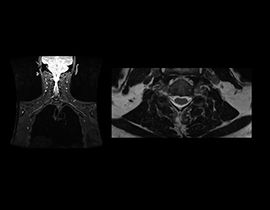

Diese Komplettlösung ermöglicht die Darstellung von Gehirn, Wirbelsäule, Gefäßsystem und peripherem Nervensystem mit außergewöhnlichem Gewebekontrast. Mit ihren bewegungsunempfindlichen Techniken ermöglicht sie die automatische Ausrichtung mit nur einem Klick und stellt eine vollständige Neurologie-Lösung vom Scan bis hin zur Nachbearbeitung bereit.

NeuroWorks beinhaltet auch Cube, unsere Suite für volumetrische 3D-Bildgebung, die für jedes System Standard ist. Mit dieser Anwendung können Sie die Hirn- und Rückenmarkflüssigkeit und entweder die weiße oder die graue Substanz unterdrücken, um die Sichtbarkeit von Läsionen zu erhöhen.